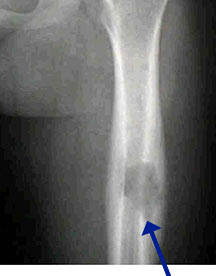

- May arise from any bone and any site within a bone (epiphyseal, metaphyseal, diaphyseal)

- Radiographically variable appearance: may appear benign (geographic) or malignant (permeative or moth eaten)

- Majority of patients are cured by curettage or intralesional injection of a steroid

- Curettage and bone grafting for long bones and weight bearing bones at risk for fracture

- Intralesional steroids for non weightbearing bones

- Complete healing may take a year